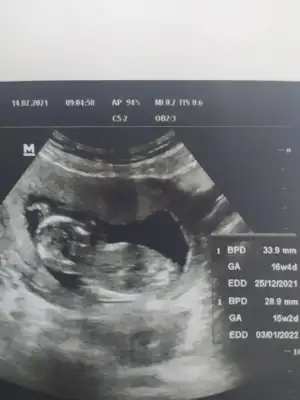

Selamlar bugun doktora gittim 14+2deyiz cinsiyet goremedim dedi var mi tahmini olan 🙈

T tulperde ayrica rica edebilir miyim 🙏🤭

Eklentiler

• IMG_20210714_092335.webp

IMG_20210714_092335.webp

21,2 KB · Görüntüleme: 82